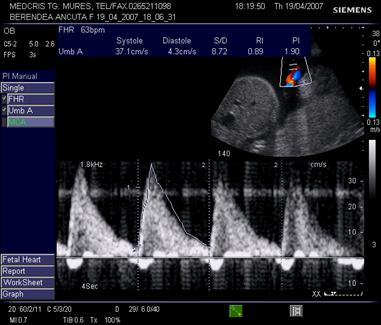

Aspecte patologice anormale ale examenului Doppler ombilical

Daca rezistenta placentara creste, viteza reziduala in diastola se reduce, iar IR si IP cresc.

Aspectul IR este patologic peste percentila 90 din curba de referinta, daca frecventa cardiaca fetala este normala. De asemenea, daca doua examinari la 4 sapt. interval indica o stagnare a IR sau o scadere a fluxului diastolic, situatia este patologica.

In situatii de rezistenta placentara si mai crescuta, se poate ajunge la flux diastolic absent, sau componenta diastolica negativa (reverse flow) ceea ce indica o alterare grava a hemodinamicii fetoplacentare. [3,14,17]